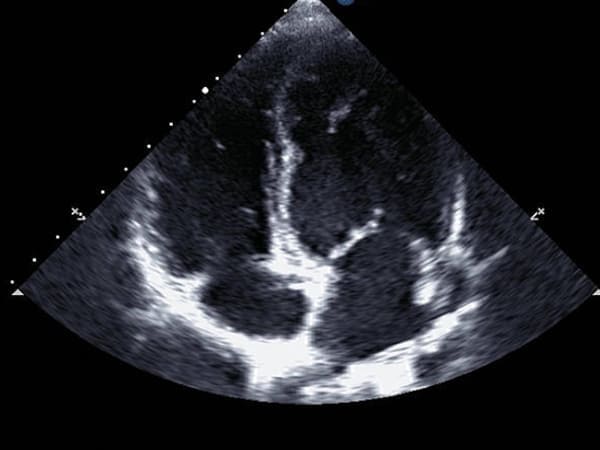

Ecocardiogramas

Es el estudio de imagen cardiaca que se solicita de primera instancia para evaluación del corazón, ya que aporta información completa, rápida y costo beneficio eficiente....